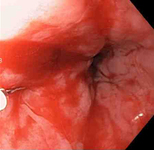

Mallory-Weiss tear

A through-the-scope clip deployed in the center of the lesion (no previous epinephrine was infused in this case)

From the collection of Juan Carlos Munoz, MD, University of Florida